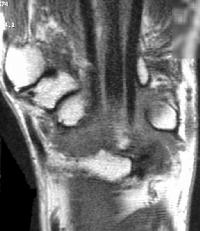

Sections through the carpal tunnel -  looking for a hook of hamate fracture or tendon discontinuity - were read as normal, although there may be a subtle signal irregularity through the hook of the hamate:

Click for larger image

Is that a tendon rupture adjacent to the pisotriquetral joint?